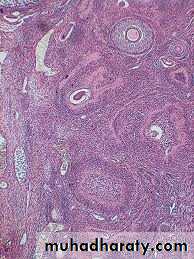

They are almond-shaped bodies (3 x1.5x1 cm).Each ovary is covered by a simple cuboidal epithelium, the germinal epithelium, continuous with the mesothelium and overlying a layer of dense connective tissue capsule the tunica albuginea, responsible for the whitish color of the ovary.

It consists of the cortex (stroma) a region filled with a highly cellular connective tissue stroma and many ovarian follicles.The internal part is the medulla, which contains loose connective tissue blood vessels entering the organ through the hilum from mesenteries suspending the ovary.

Ovarian Follicles

They consist of an oocyte surrounded by one or more layers of epithelial cells.They are embedded in the cortex of the ovary.

Ovarian follicles are

1.Inactive – Primordial follicles2.Growing follicles – include

Unilaminar primary follicle

Multilaminar primary follicle

Secondary (Antral) follicle

3.Mature (Graafian) follicle

(1)primordial follicles

(1)consist of a primary oocyte enveloped by a single layer of the flattened follicular (granulosa) cells(2)They are inactive follicles.

(3)These follicles are found in the superficial areas of the cortex (under tunica albugenia).

(4)The oocyte in the primordial follicle is a spherical cell about 25 micrometer in diameter, with a large nucleus and in the first meiotic prophase.

(2)Growing follicles(A) unilaminar primary follicles

(1) Oocyte is larger(2) Follicular (granulosa) cells become cuboidal then columnar

(B) Multilaminar primary follicles

• 1.The follicular cells continue growth, forming a stratified epithelium, termed granulosa cells• 2.the follicle is surrounded by basement membrane.

• 3.Between the oocyte and granulosa cells, a layer of extracellular material called the zona pellucida develops, consist of glycoprotein secreted by the oocyte. Zona pellucida(B) Multilaminar primary follicle

4. the stromal cells immediately around the follicle differentiate to form the follicular theca.This layer subsequently differentiates further as two layers: a well-vascularized endocrine tissue, the theca interna, and a more fibrous outer theca externa containing smooth muscle and fibroblasts

(C)Secondary (antral) follicles

1.They move deeper in the ovarian cortex.2.Small spaces develop within the granulosa layer as the cells secrete follicular fluid (or liquor folliculi). This fluid accumulates, the spaces gradually coalesce, and the granulosa cells reorganize themselves around a larger cavity, the antrum.

antrum formation pushes oocyte and the surrounding granulosa cells to one side of follicle forming, the cumulus oophorus.The remaining granulosa cells are called membana granulosa

(3) Mature (graafian) follicles

During each menstrual cycle, usually one follicle grows much more than the others and becomes the dominant follicle, while many of the other follicles eventually enter atresia.The dominant follicle usually reaches the most developed stage of follicular growth and may undergo ovulation.

1.reaches a diameter of 20-30 mm or more prior to ovulation,2.large enough to protrude from the surface of the ovary and be detected by ultrasound imaging.

3.The antrum increases greatly in size by accumulating follicular fluid

4.the oocyte adheres to the wall of the follicle through the cumulus oophorus of granulosa cells.

5.The membrana granulosa layer becomes thinner.6.The granulosa cells immediately around and linked to the oocyte make up the corona radiata and accompany the oocyte when it leaves the ovary